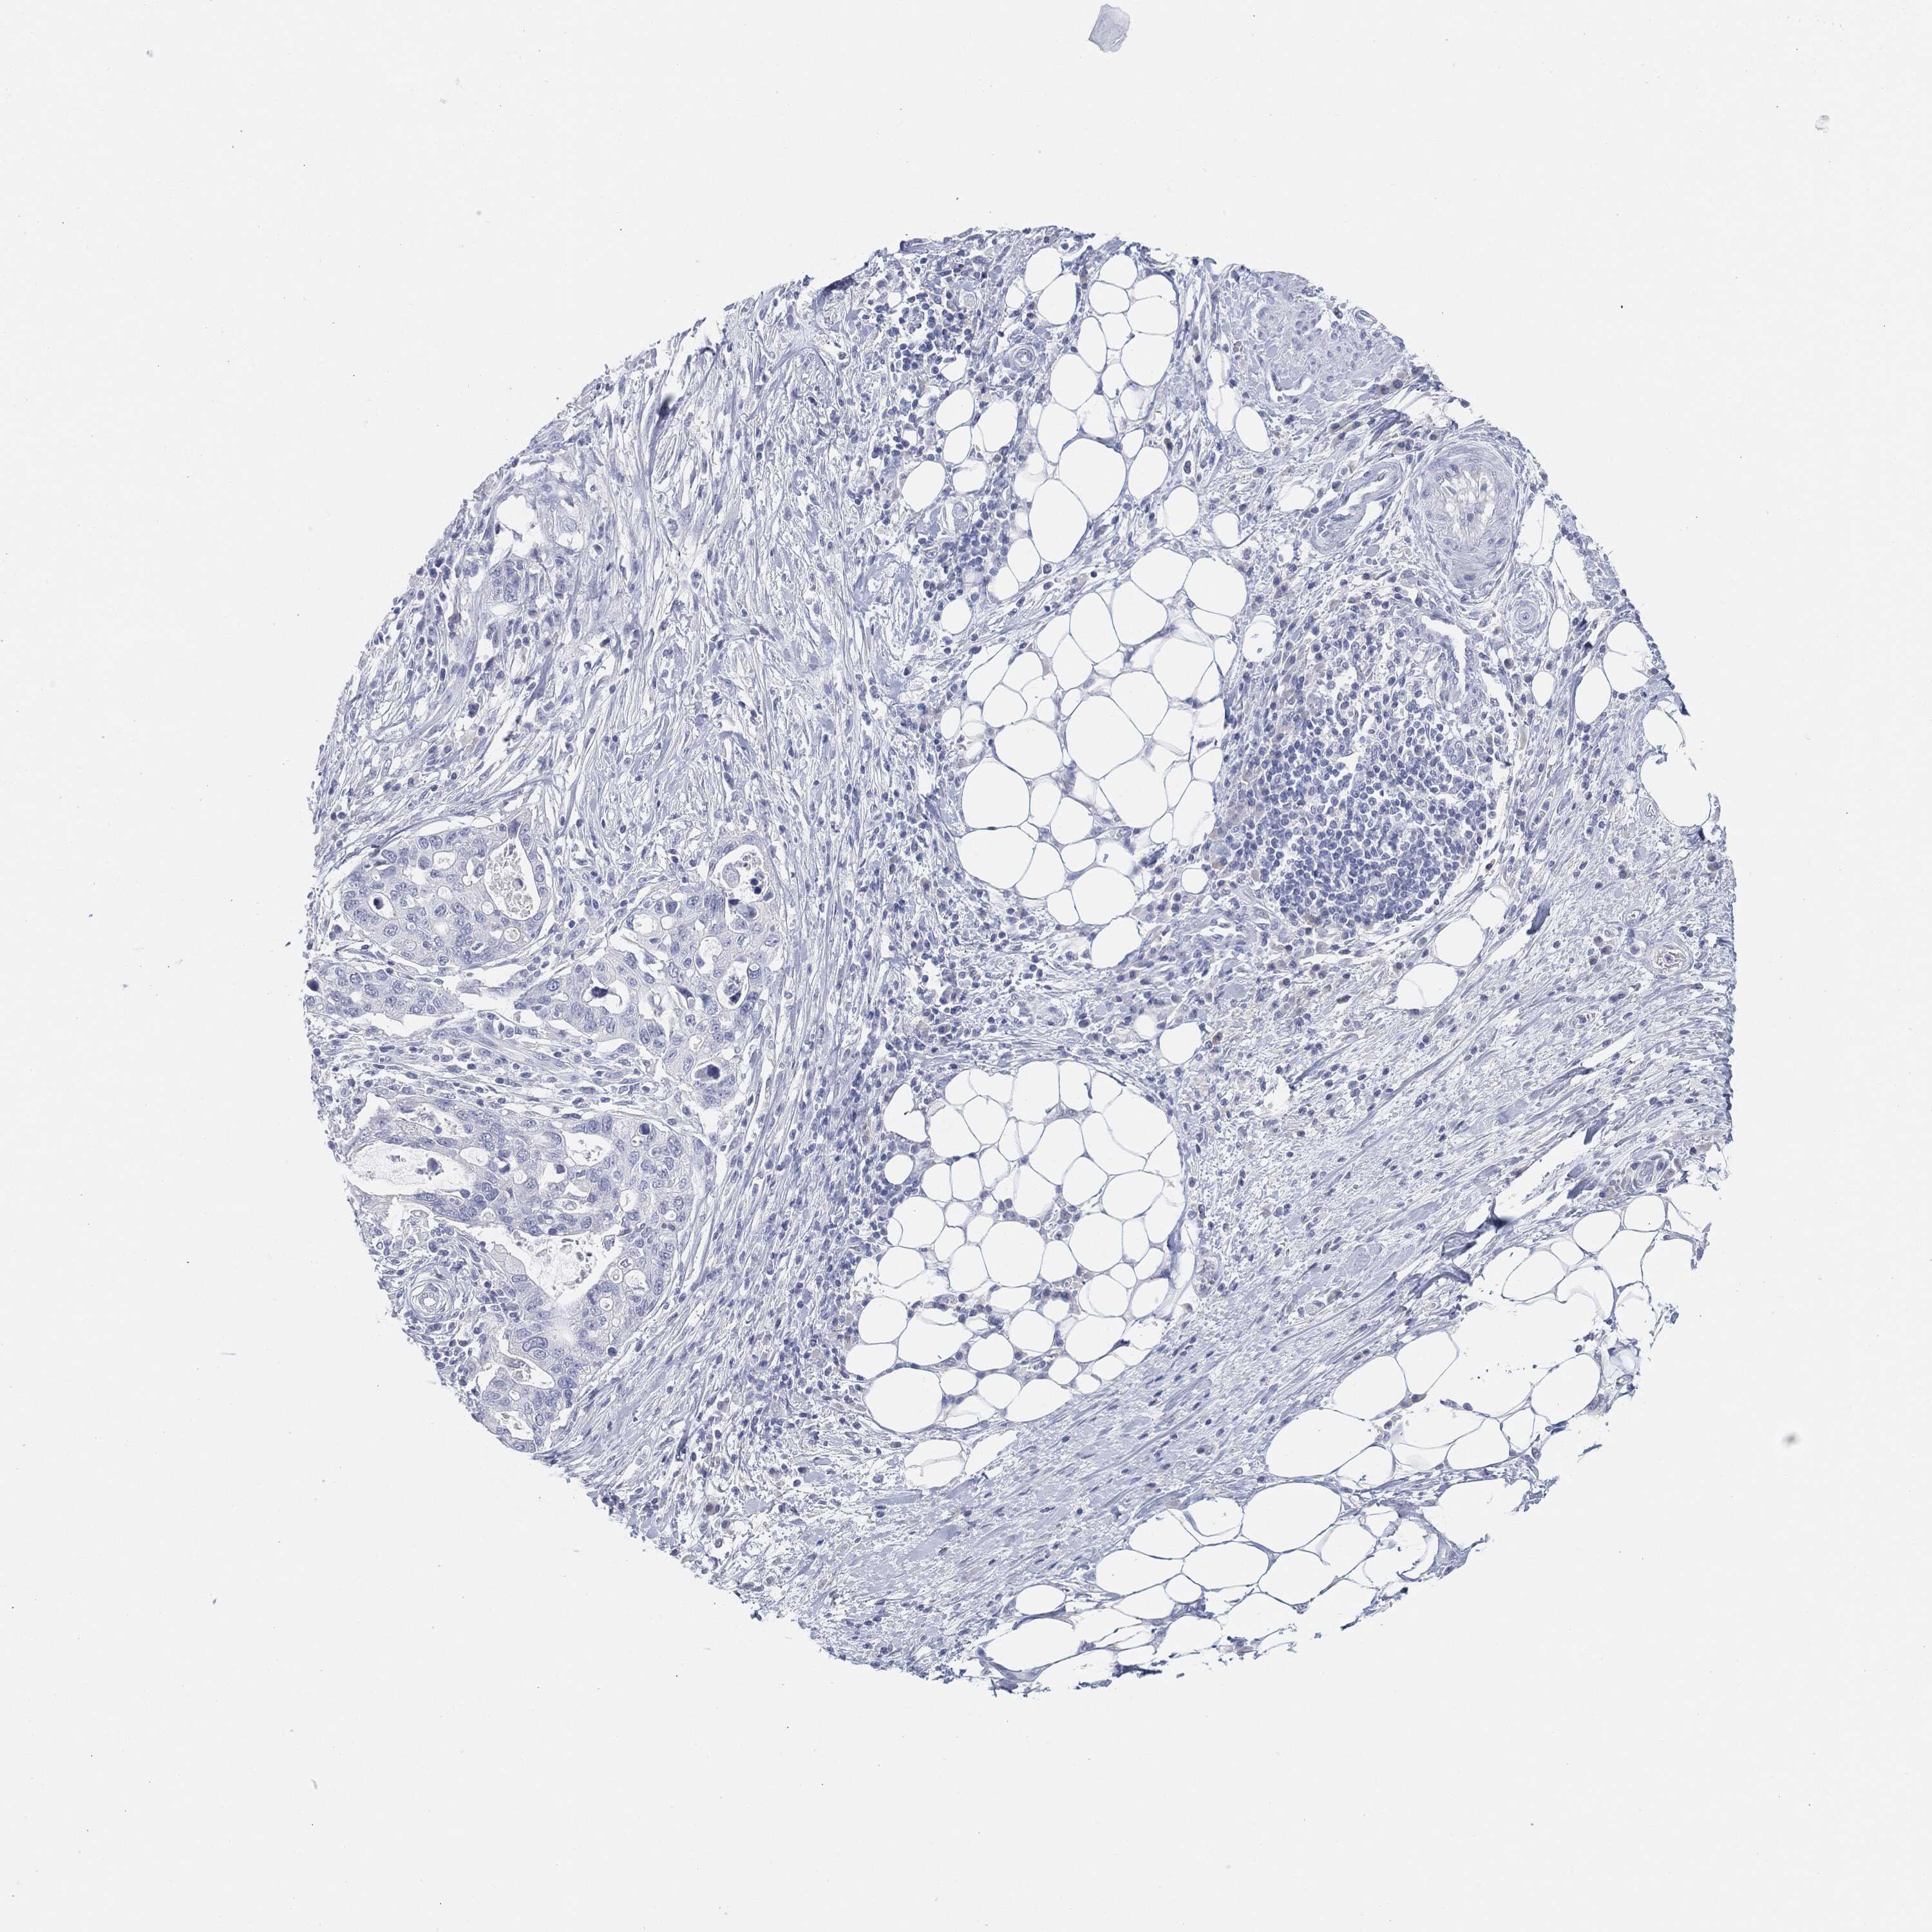

STOMACH CANCER - Protein expressioni

A mouse-over function shows sample information and annotation data. Click on an image to view it in a full screen mode. Samples can be filtered based on level of antibody staining by selecting one or several of the following categories: high, medium, low and not detected. The assay and annotation is described here.

Note that samples used for immunohistochemistry by the Human Protein Atlas do not correspond to samples in the TCGA dataset.

Antibody stainingi

Antibody staining in the annotated cell types in the current human tissue is reported as not detected, low, medium, or high, based on conventional immunohistochemistry profiling in selected tissues. This score is based on the combination of the staining intensity and fraction of stained cells.

Each image is clickable and will lead to virtual microscopy that enables deeper exploration of all samples and also displays staining intensity scores, fraction scores and subcellular localization as well as patient and tissue information for each sample.

Antibody HPA031634

Antibody CAB080501

Antibody CAB080502

Antibody CAB080503

Adenocarcinoma, NOS

Adenocarcinoma, High grade